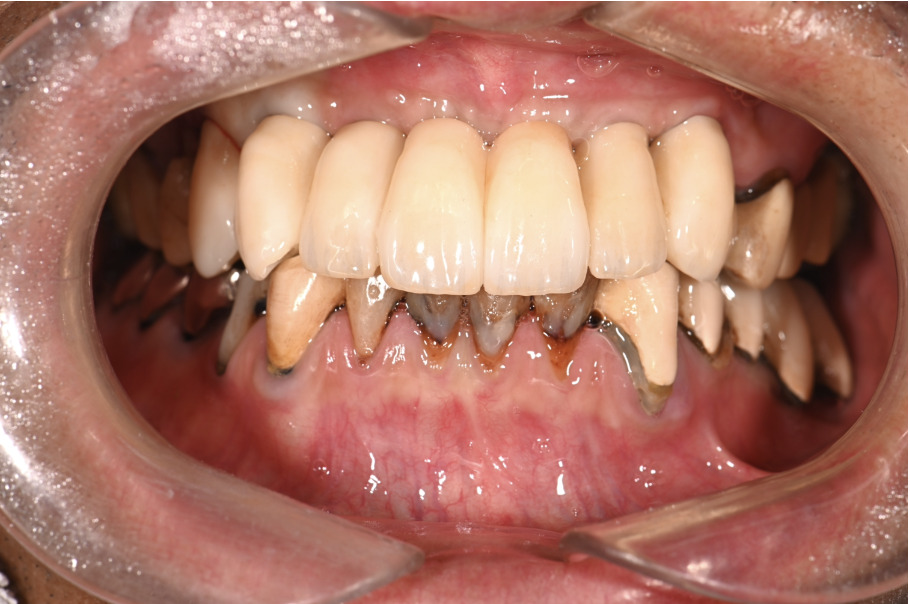

| 主訴 | 上の歯がぐらぐらする |

|---|---|

| 治療内容 | 上顎の歯が重度の歯周病のため全て抜歯し、

上顎に対するインプラント治療を行った。 午前中にインプラントの土台を入れ、夕方に上部構造(歯)を装着。 1日で噛めるようになる治療法。 |

| 治療期間 | 1日 |

| 治療費 | 250万円 |

| 治療 リスク | インプラント治療後2、3日はやや痛みを伴うことがあります。 |